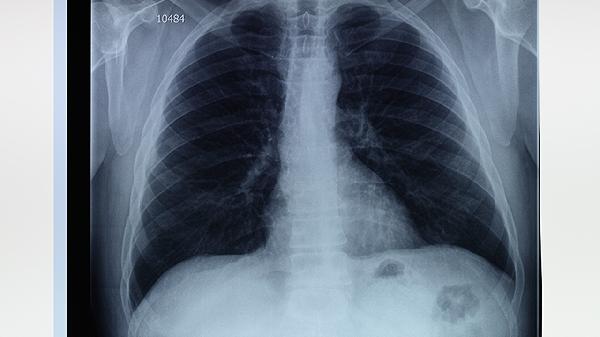

鼻癌最明显的症状包括鼻塞、鼻出血、面部疼痛或麻木以及持续性耳鸣。治疗需根据病情选择手术、放疗或化疗,早期发现和治疗对预后至关重要。鼻癌的发生与遗传、环境因素、病毒感染及长期吸烟饮酒密切相关,了解症状并及时就医是关键。

1、鼻塞是鼻癌的常见症状,通常表现为单侧或双侧鼻腔阻塞,可能伴随黏液或脓性分泌物。若鼻塞持续不缓解,需警惕鼻癌可能,建议尽早就医进行鼻内镜检查或影像学检查,明确诊断后选择手术治疗、放疗或化疗。

2、鼻出血是鼻癌的另一典型症状,可能表现为反复性或持续性鼻出血,尤其是单侧鼻腔出血。若出血量较大或频繁发生,需及时就医,通过鼻内镜或CT检查明确病变范围,治疗方法包括局部止血、手术切除或放射治疗。

3、面部疼痛或麻木可能与鼻癌侵犯周围神经或组织有关,表现为持续性或阵发性疼痛,伴有面部感觉异常。若出现此类症状,需尽早就医,通过影像学检查明确病变范围,治疗方法包括手术切除、放疗或靶向治疗。

4、持续性耳鸣可能与鼻癌侵犯耳部结构或压迫神经有关,表现为单侧或双侧耳鸣,伴有听力下降。若耳鸣持续不缓解,需及时就医,通过听力测试或影像学检查明确病因,治疗方法包括手术切除、放疗或药物治疗。

鼻癌的症状多样,早期发现和治疗对预后至关重要。若出现鼻塞、鼻出血、面部疼痛或麻木、持续性耳鸣等症状,应及时就医,通过专业检查明确诊断,并根据病情选择手术、放疗或化疗等治疗方案。了解鼻癌的常见症状,提高警惕,有助于早期发现和治疗,改善预后。